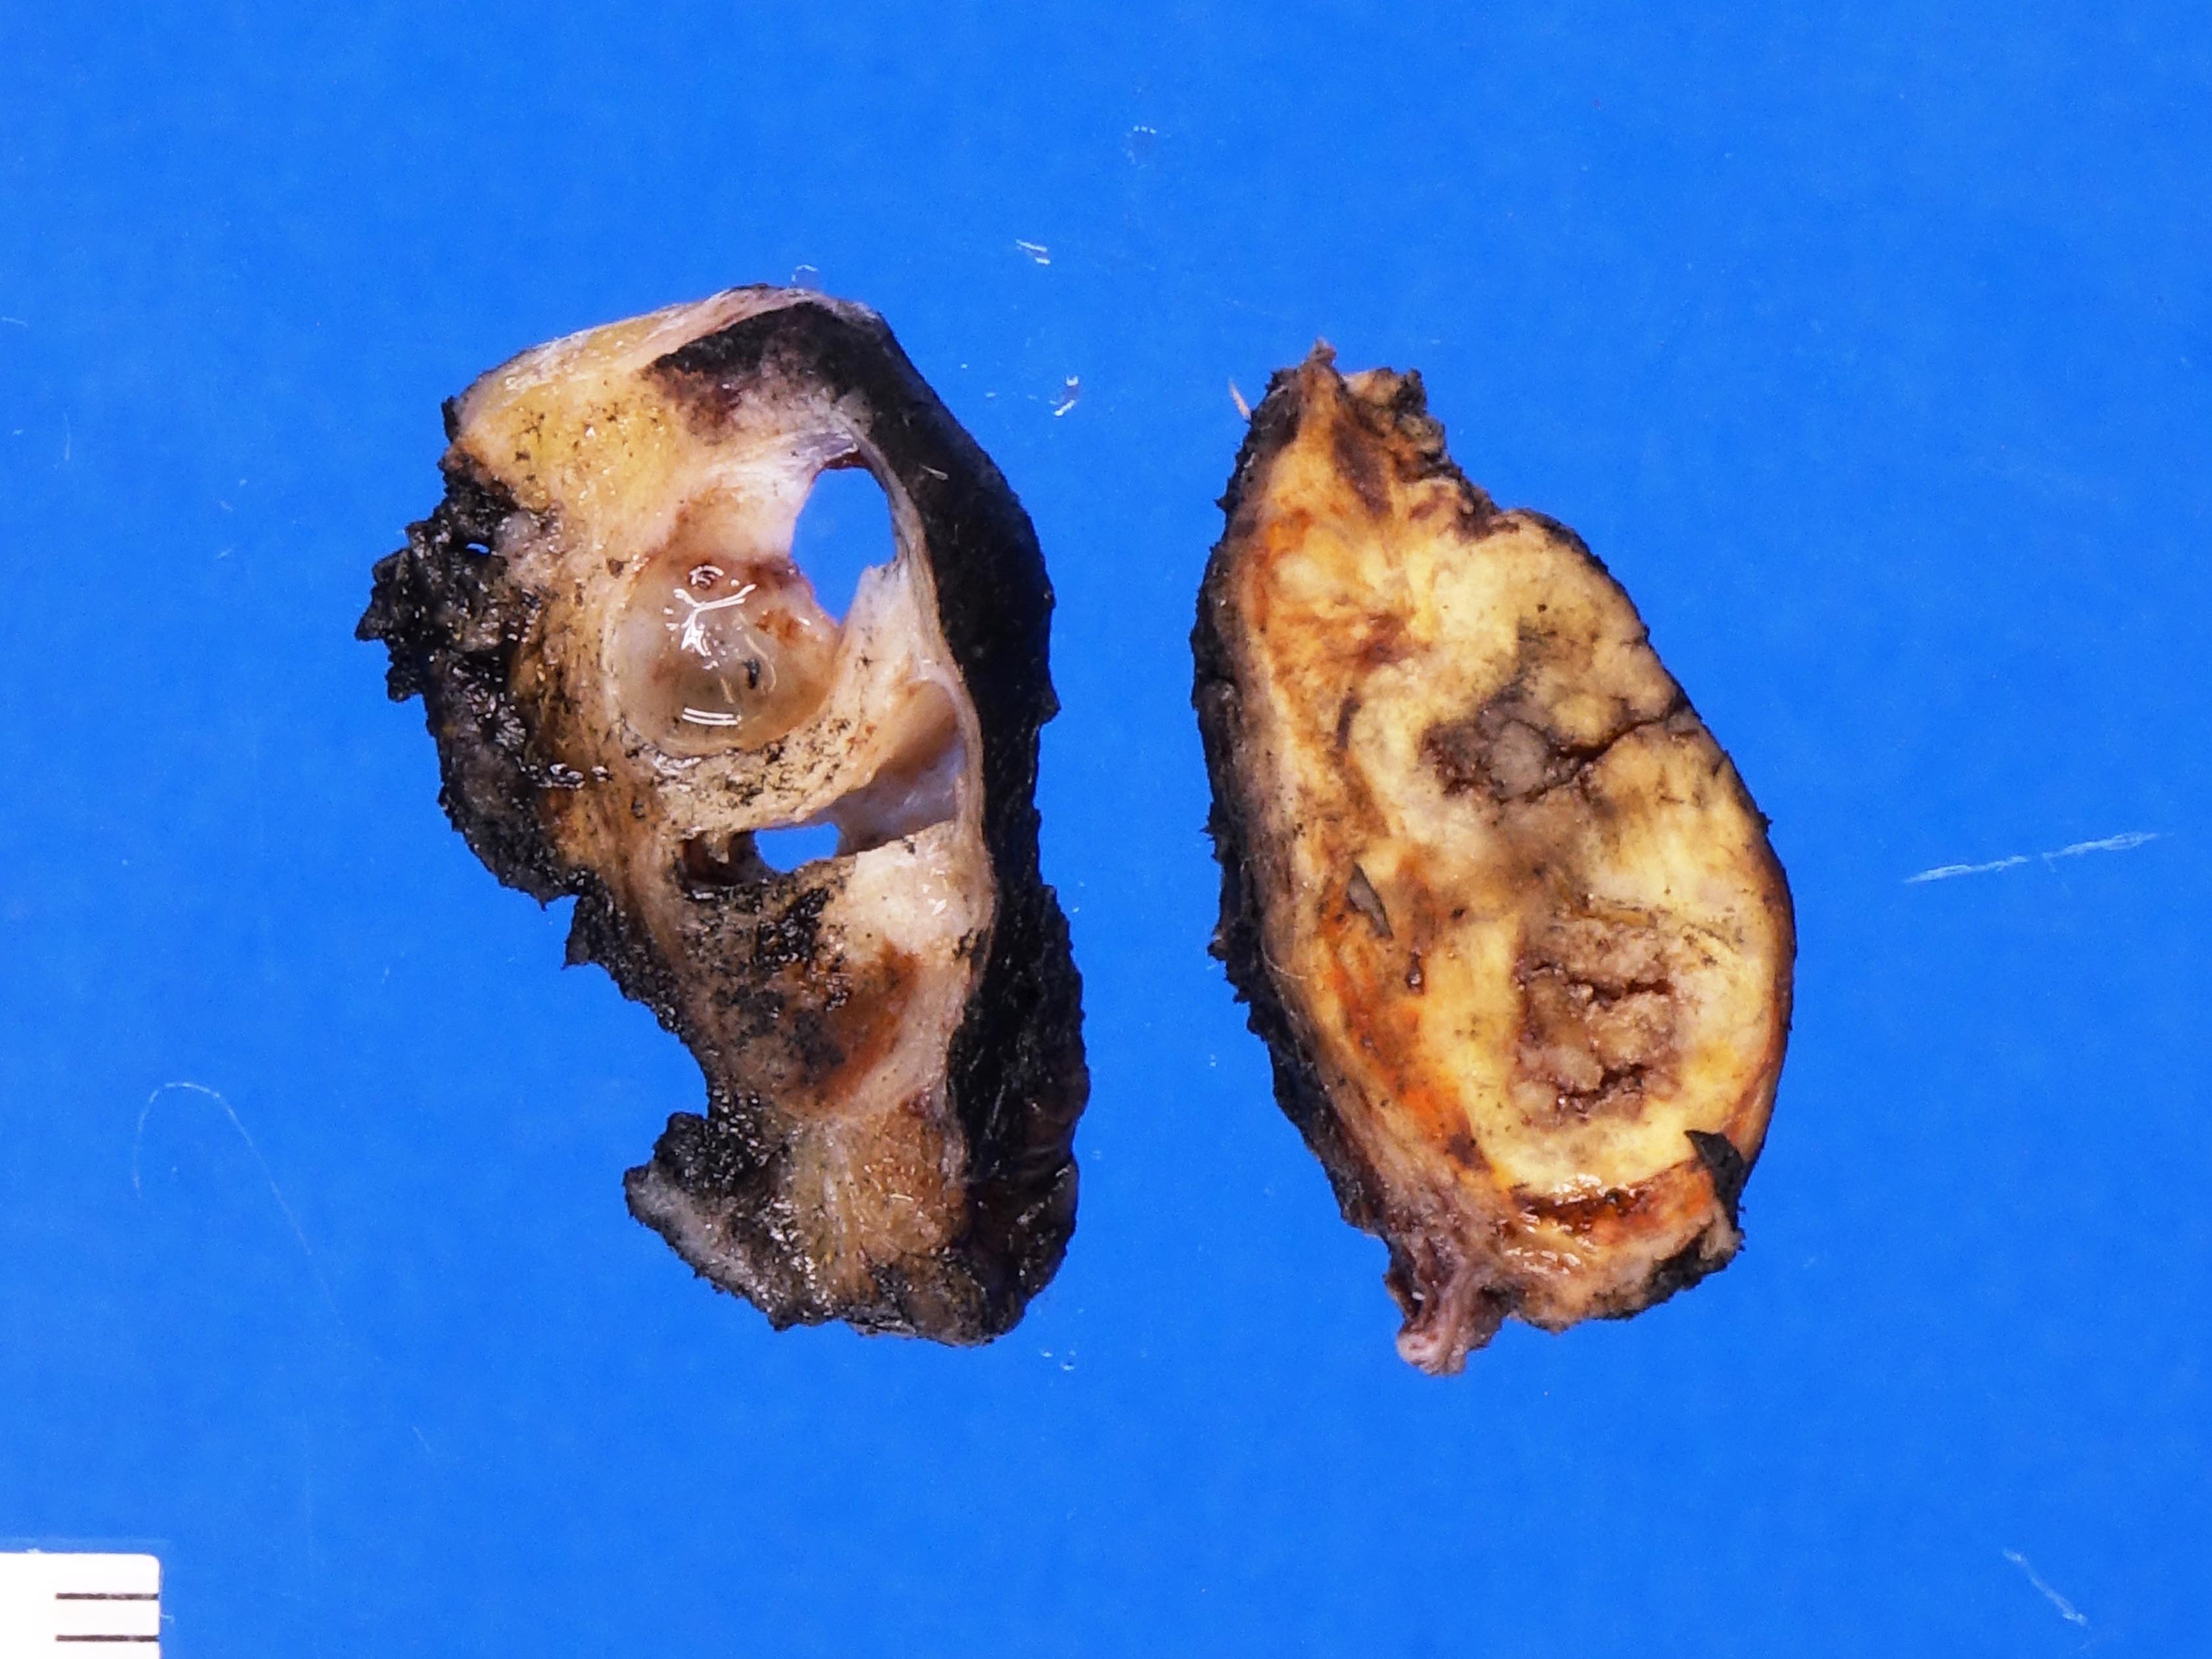

Gross images

Contributed by Debra L. Zynger, M.D.

Complete regression (pT0)

Germ cell neoplasia in situ only (pTis)

Partial regression (pT1)

Teratoma (pT1)

Teratoma and EC (pT1)

Seminoma (pT1a)

Seminoma (pT1b)

Mixed germ cell tumor (pT2)

Seminoma (pT2)

No residual node tumor (ypN0)

Discontinuous spermatic cord (pM1)